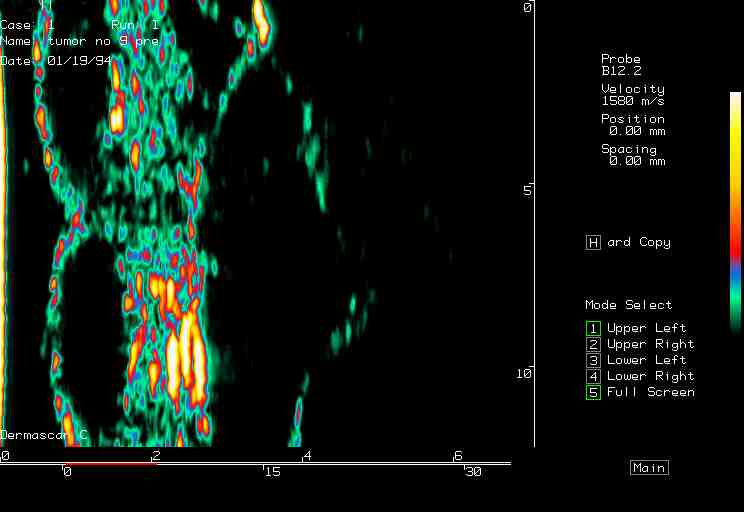

| Tumors |  BCC on the ear |

BCC, various sites |

BCC pre PDT |

BCC post PDT |